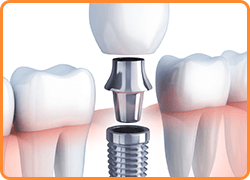

インプラントとは、歯を失った部分にチタン製の人工歯根を埋め込み、その上から人工歯を装着する治療方法です。

人工歯根は顎の骨としっかりと結合するため、入れ歯のようにズレや外れることを気にせずに食事や会話を楽しむことができます。

また、ご自身の健康な歯を削る必要がないので安心して治療を受けていただけます。

外科的な手術が必要になりますので、ご興味のある方はまずはお気軽にご相談ください。

インプラントは、フィクスチャー(人工歯根)とアバットメント(連結部分)と上部構造(人工の歯)で構成されています。

顎の骨にしっかり埋め込むので、ご自身の歯のような感覚です。

インプラント手術

手術は麻酔をしてから行いますので、痛みを感じることはほとんどありません。処置時間は約30分~120分ほどです。

治療期間

フィクスチャーと骨が結合するまで時間を置きます。種類やお口の状況によって異なりますが、3ヶ月から6ヶ月ほどで結合することがほとんどです。

アバットメント、上部構造の装着

アバットメントと上部構造を装着します。

定期的なメインテナンス

回復した口腔状態をできるだけ長く保っていただくために、メインテナンスを定期的に行うことが大切です。